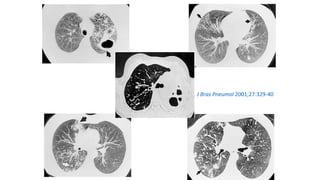

J Bras Pneumol 2001;27:329-40

J Bras Pneumol 2004;30:S 3-85

Baum´s Text Pulm Dis 5th ed

Miliary pattern

Intersticial Randomic micronodular distribution